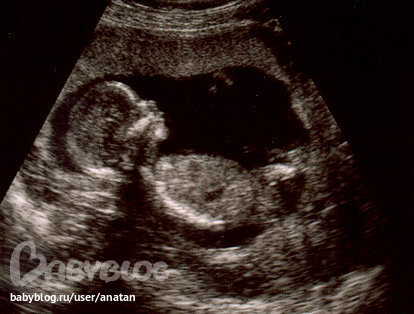

счастливые!!! 28 недель

Наша бусинка такая хорошенькая, все в норме развитие плода идет хорошо)))